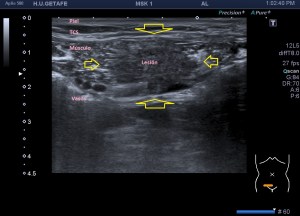

Durante la exploración de una eco de abdomen en el contexto de un paciente que acude por elevación de transaminasas observo una imagen heterogénea, irregular, con una pared marcadamente calcificada, bilobulada de gran tamaño que medí en dos partes ya que me pareció claramente que estaban diferenciadas.

Una de ellas, la primera, era mucho más hiperecogénica y más pequeña, su centro estaba mas calcificado, su sombra acústica posterior era mucho más acuciada y llamaba más la atención. Justo al lado, otra lesión de mayor tamaño, su calcificación era mucho más sutil y más periférica delimitando una LOE hipoecogénica de un tamaño muy importante, adyacente a la más pequeña, como he comentado previamente. Ambas sin señal Doppler.